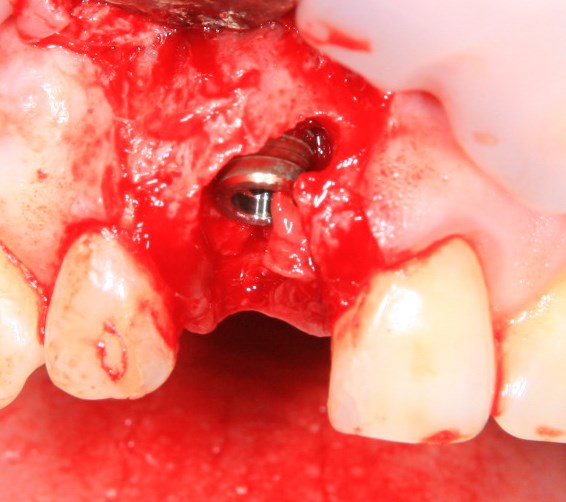

Немедленная имплантация — оптимальное решение в любой клинической ситуации